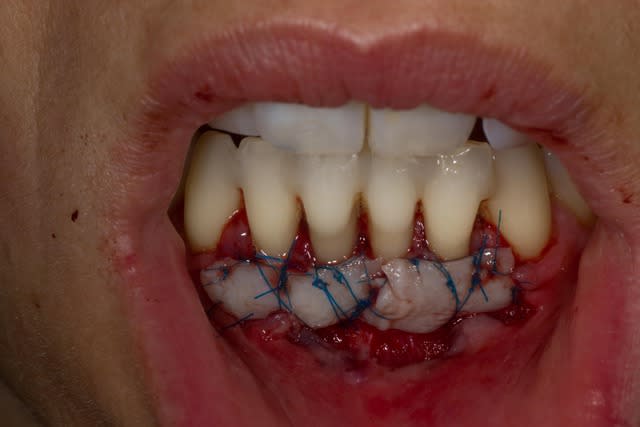

Comme on voit pas bcp de muco sur eugenol

P'tite 23 qui montrait trop de racine

Les 2 dernières photos sont à la dépose des fils (14 jours)

Il y a une "sling suture" pour la traction, le point collé au compo, est en plus, pour tester ;-)

Voici un cas similaire, encore une 23, perte de tissu plus grande, pas de point suspendu avec compo, seulement 2 "sling-suture".

Greffon tracté sous lambeau en mésial et distal comme le cas précédent avec sutures.

Pas d'incision vertical en mésial, surtout que la 22 est un implant, placé trop apical, donc risque de perdre papille distal de 22 +++. Petite incision vertical en distal de 23, pour tracter le lambeau.